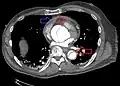

Computed tomography

Computed tomography angiography is a fast, non-invasive test that gives an accurate three-dimensional view of the aorta. These images are produced by taking rapid, thin-cut slices of the chest and abdomen, and combining them in the computer to create cross-sectional slices. To delineate the aorta to the accuracy necessary to make the proper diagnosis, an iodinated contrast material is injected into a peripheral vein. Contrast is injected and the scan performed using a bolus tracking method. This type of scan is timed to injection to capture the contrast as it enters the aorta. The scan then follows the contrast as it flows through the vessel. It has a sensitivity of 96 to 100% and a specificity of 96 to 100%. Disadvantages include the need for iodinated contrast material and the inability to diagnose the site of the intimal tear.

CT with contrast demonstrating aneurysmal dilation and a dissection of the ascending aorta (type A Stanford)- Chest CT with descending (type B Stanford) aortic dissection (red circle)

Type A dissection with pericardial effusion as a result.